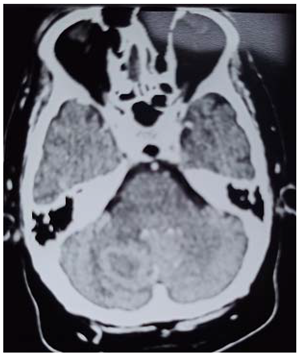

This is 18years Sudanese young female, university student, an otherwise healthy before, presented to neurosurgery emergency unit with history of rabidly progressing headache for 6 months duration, few weeks before her appearance she exhibit visual blurring that end in decrease visual acuity in both eyes, she has inability to walk steady.

Neurological examination, revealed conscious patient, with just perception to light and there was increase tone and exaggerated reflexes on both lower limbs.

Preprints 114904 i001

Operation: Before the decision of surgery, we talked to the patient and her family clearly about the surgery complications and post operative outcome. Through left tempro- parito-occipital craniotomy, the tumor was macroscopically totally resects. It was sub cortical, well circumscribed ill define capsule, extended deeply to the underlining temporal horn of the lateral ventricle .Dural graft was taken from the tempralis fascia and was closed in water tide.

Patient was fully recovered from anesthesia and was taken to the ICU on nasal oxygen mask.

Histopathology

Brain tubeclomata ( extra pulmonary tuberculosis)

Patient was put on anti-tuberculosis according to the international protocol, and discharged free of headache, can see objects.